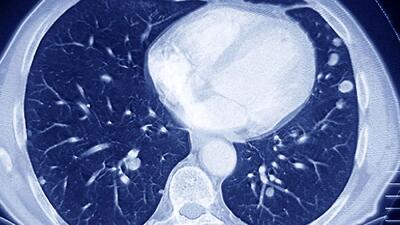

با افتتاح و بهرهبرداری از دستگاه پتاسکن (PET Scan) در هرمزگان، این استان به جمع معدود استانهای کشور پیوست که این خدمت تخصصی تصویربرداری پزشکی را با تعرفه دولتی به بیماران ارائه میدهند.

چند پروژه درمانی و خدماتی در فومن از جمله افتتاح دستگاه CT اسکن بیمارستان امام حسن مجتبی(ع)، آغاز عملیات اجرایی احداث بخش دیالیز، افتتاح پد بالگرد و غیره به بهره برداری رسید.

کردستان در ردیف ۶ استان برخوردار از دستگاه پتاسکن( تشخیص سرطان)

رئیس دپارتمان پزشکی هستهای پزشکی هستهای و تصویربرداری بیمارستان کوثر سنندج گفت: کردستان ششمین استاد کشور در دریافت دستگاه pet scan پیشرفته از نوع ۲۰۲۱ است که نشان از اهمیت و توجه به تجهیزات پزشکی پیشرفته در استان است.